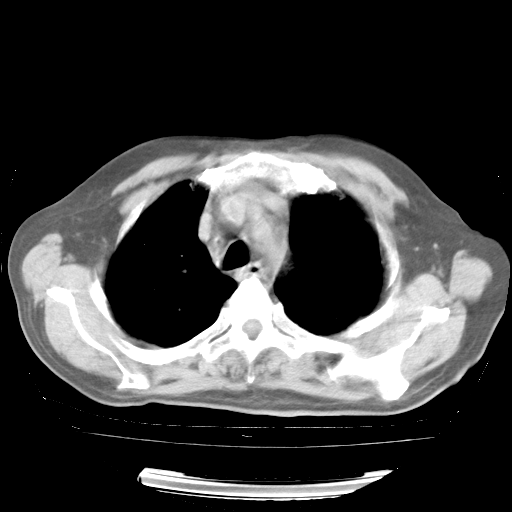

4月28日肺部CT

个人阅读4.14日肺部CT平扫:纵隔窗无异常,但肺窗示:双下肺内、后基底段有片絮状侵润影,部位以后基底段为著,以间质改变为主,呈急性肺泡炎征像,和首次住院影像学有相似之处。仅是个人读片,明日请相关专家再读片哈。其它建议同上。

1、108#的是4月14日的胸部CT(发此贴时还没看着28日的CT)。14日的胸部CT其实已经出现改变(如108#所述),个人认为28日的胸部CT除纵膈窗疑似有双侧胸膜增厚或少量胸积液(可行胸部B超明确)外,与4月14日对照病变有所加重;2、已经给予“异烟肼、利福平、乙胺丁醇”抗痨治疗?如果是,甲强龙80mg可缓慢减量;如果环磷酰胺已停用,暂不使用;3、中性粒细胞92%,明显升高,目前体温情况?注意合并细菌感染可能,使用左氧氟沙星情况下,是否联用B-内酰胺类抗菌药物?另外是查免疫全套非风湿全套。